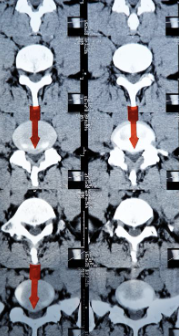

허리디스크는 디스크가 터져서 신경을 누를 경우 생기는 것으로 보통 4,5번에서 많이 일어나고 디스크가 터진 양이 적다면 터진 순간부터 수분이 날아가면서 양이 많이 없어지는데 그렇지 않고 양이 많을 경우 극심한 고통이 생깁니다.

고통이 덜한 환자들은 재활 , 물리, 약물치료 등을 통해 진행하지만 특정 원인이나 흘러나온 디스크가 신경을 많이 눌러 극심한 고통이 있다면 빠른 수술을 진행되는 것이 좋습니다.